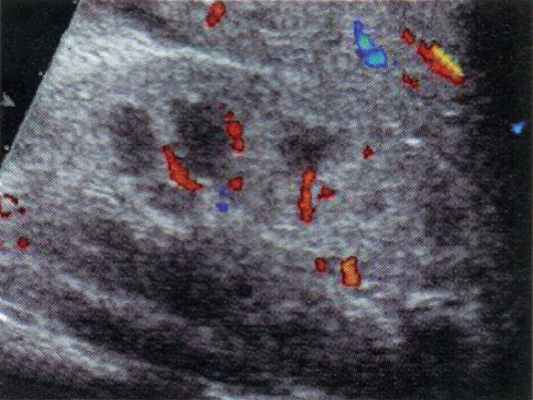

По мере развития патологического процесса, при переходе заболевания в фазу "глаукомы" почки, кровоток в ней существенно изменяется. Сначала появляется большее количество визуализируемых интерлобарных сосудов (диастолический антеградный компонент артериального ренального кровотока обычно еще полностью не восстанавливается (рис. 4). Позднее происходит полное восстановление диастолической антеградной составляющей ренального артериального кровотока на уровне магистральных, сегментарных и интерлобарных артерий, однако дуплексное допплеровское сканирование показывает отсутствие кровотока в кортикальном слое почки (рис. 5). Клинически эта сонографическая картина соответствует сохраняющейся высокой азотемии, анурии. Через 2-5 дней после восстановления резистивных характеристик артериального кровотока дети обычно начинали мочиться самостоятельно, однако азотемия сохранялась (еще 3-10 дней), и дети продолжали нуждаться в проведении диализа.

а) Дуплексное допплеровское сканирование почки - восстановление кровотока в медуллярном слое при сохранении ишемии кортикального слоя паренхимы.

б) Допплерография почки в эту фазу заболевания.

а) Дуплексное допплеровское сканирование почки в фазу систолы.

б) Дуплексное допплеровское сканирование почки в фазу диастолы.

в) Допплерография на уровне интерлобарной артерии почки.